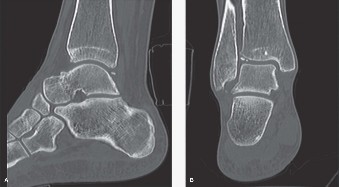

Clinical and Radiographic Imaging

- CT Scan: Provides detailed information on bone morphology, osteophyte burden, cystic lesions, and bone stock. Critical for assessing axial rotation, articular surface integrity, and identifying any talar avascular necrosis. It aids in preoperative templating and identifying potential challenges for bone cuts.